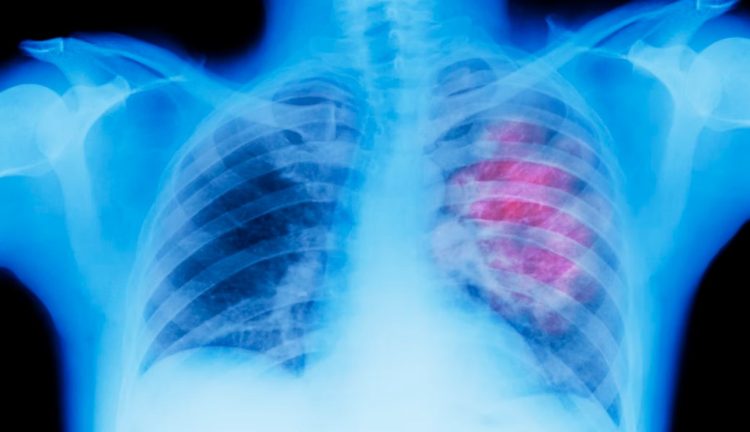

New AI Tool Predicts Cancers Better, May Catch Them Far Earlier